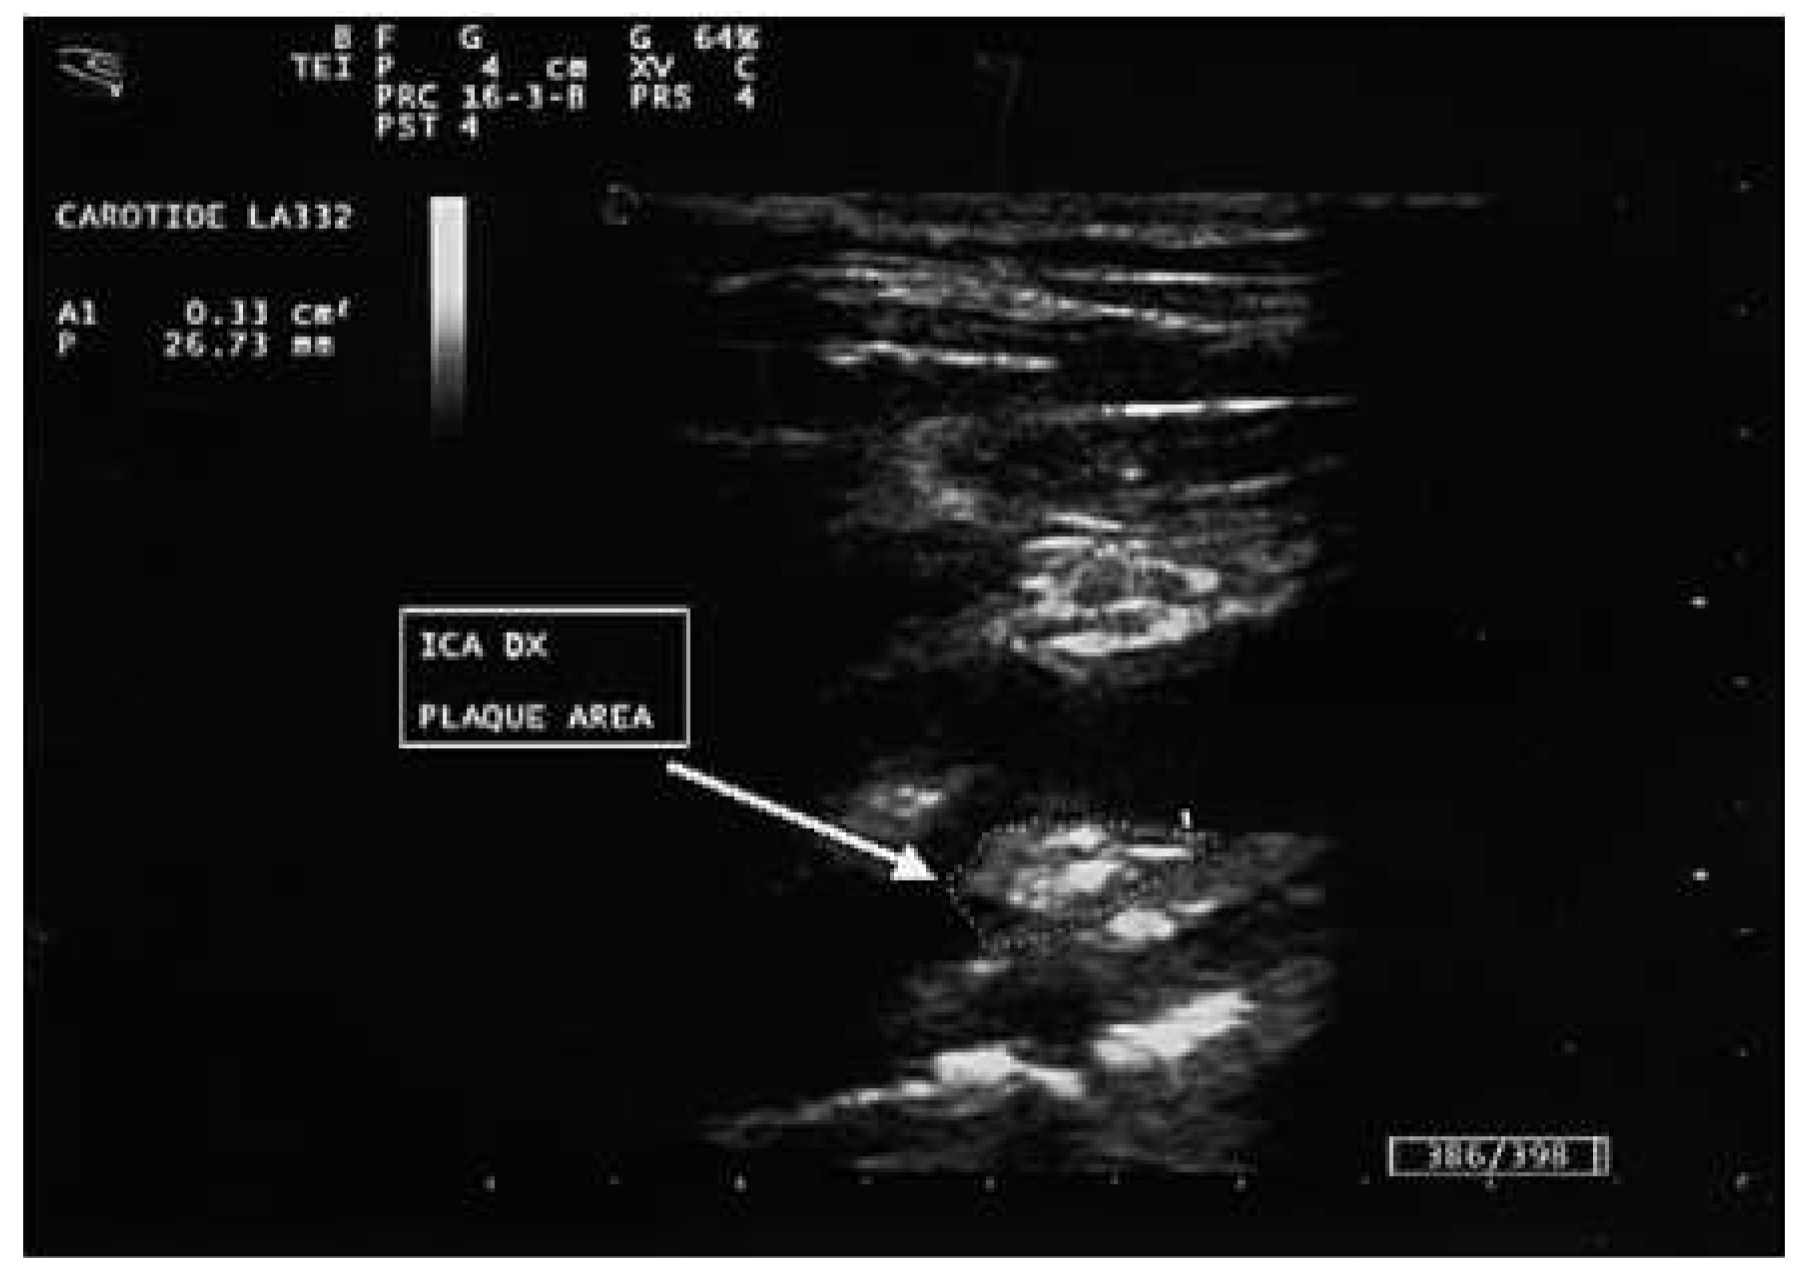

- Role of carotid plaque in cardiovascular risk prediction: comparison with CIMT